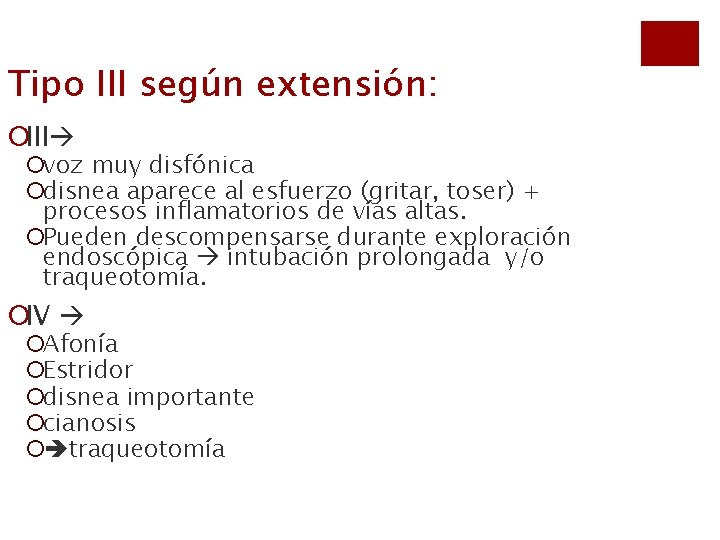

Tipo III según extensión: ¡III ¡voz muy disfónica ¡disnea aparece al esfuerzo (gritar, toser) + procesos inflamatorios de vías altas. ¡Pueden descompensarse durante exploración endoscópica intubación prolongada y/o traqueotomía. ¡IV ¡Afonía ¡Estridor ¡disnea importante ¡cianosis ¡ traqueotomía